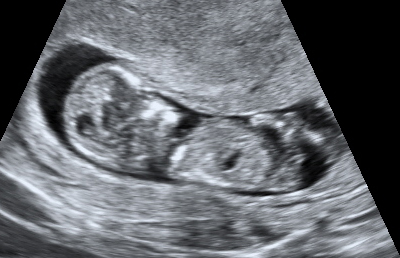

I have attached two images here from my current pregnancy. The side view is from my NT scan at 11.5 weeks. If i am correct, the nub is pointing upwards which means boy. In the second image, it is a potty shot from 16.5 weeks and there is a definite protrusion. So i am unsure why she won't confirm boy at this point. I can't see it being anything else. Am i just better at seeing things than my doc? Can anyone help?